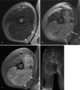

Rhabdomyolysis is a condition in which damaged skeletal muscle breaks down rapidly. Symptoms may include muscle pains, weakness, vomiting, and confusion. [Source: Wikipedia ]